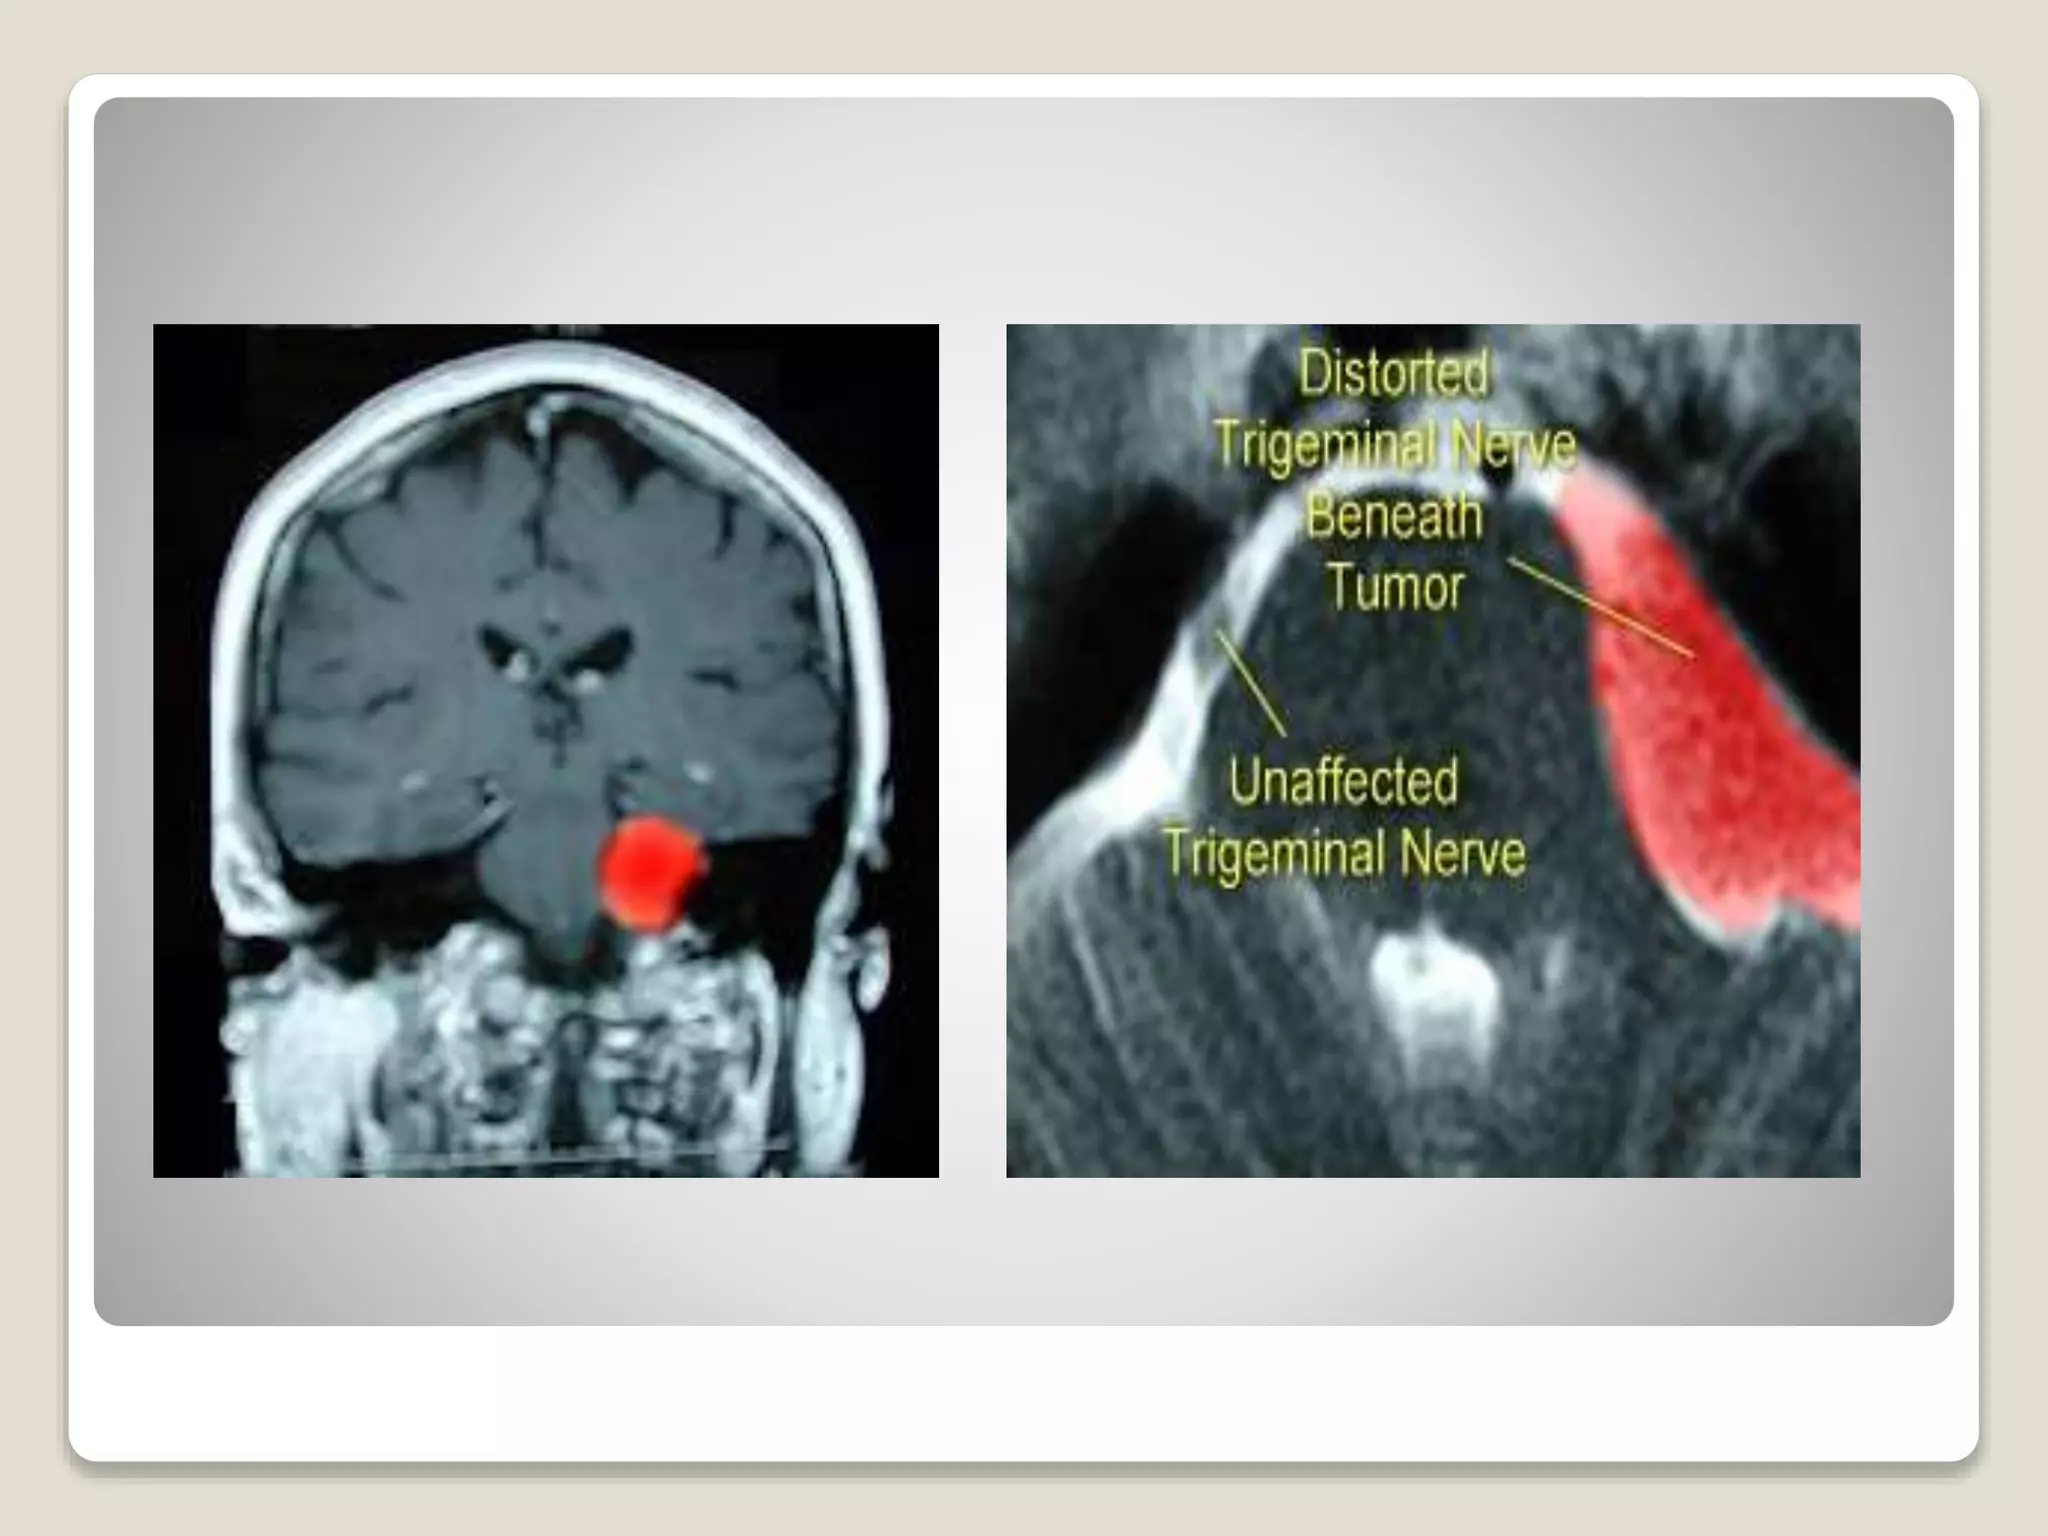

SECONDARY OR TUMOR RELATED

 TN caused by a lesion such as a tumor, tumor

can compress or distort the trigeminal nerve and

cause numbness, weakness of chewing muscles

or constant aching pain.

SECONDARY OR TUMORRELATED  TN caused by a lesion such as a tumor, tumor can compress or distort the trigeminal nerve and cause numbness, weakness of chewing muscles or constant aching pain. FAILED TRIGEMINAL NEURALGIA In case of failed surgical procedures and medications, these sufferers can suffer from additional trigeminal neuropathy as a result of destructive intervention they went.